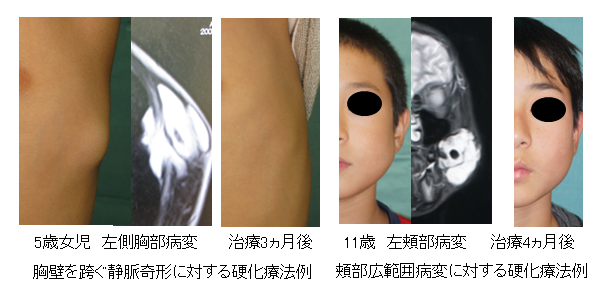

超音波検査(肝臓②) - たなべ内科クリニック(呉市広本町の。血管腫・血管奇形 ー診断と治療についてー | 横浜市立大学附属病院。03202608.jpg。他にも多数、出品しています♪よければ覗いてください☆#サクラBooks【商品について】・送料無料・即購入OK(コメント不要)・中古品ですが、通読に支障のない良好な状態です・書き込み無し・ご購入から1~2日以内に発送いたします・画像に掲載がない場合、付属品は無いものとお考えください・状態は画像にてご確認ください。血管腫 - Wikipedia。※写真と実物で色味に若干の差が出る場合がございます※本のコンディションは中身の状態を重視して判断しております。薬屋のひとりごと 1~13巻(11、12巻ドラマCD付限定特装版)。軽度のスレやキズなどの外装ダメージは記載・掲載を省略しています【ご確認事項】 •申し訳ありませんが、お値下げ交渉には対応しておりません。岩波文庫 三国志 全10巻 オリジナルパラフィン 赤帯付属 各種栞付きです。。•商品価格は、送料や手数料、メルカリ相場などを考慮し、あらかじめご検討いただきやすい金額で設定しております•お値段に関するコメントは削除させていただく場合がございます•価格は定期的に見直しておりますので、ご縁を感じていただけた際にぜひご検討くださいませ・商品状態はあくまで出品者の主観によるものです。【ポストカード付き】悪ノ娘 & 悪の大罪 全13巻セット。画像と説明をご確認の上、ご購入ください・発送は沖縄県から行います→ 地域によっては通常より到着にお時間を要することがあります→ 台風の影響で到着まで7~12日かかった事例もあります。宮部みゆき 『ブレイブ・ストーリー』愛蔵版 署名落款。気長にお待ちいただけますと幸いです・匿名配送(追跡・補償あり)でお送りします・ペット・喫煙者のいない環境で保管しておりますその他ご不明な点がございましたら、お気軽にコメントよりご質問ください「刻まれた21センチ 血管腫と共に生きる」玉元 三奈美#玉元三奈美 #玉元_三奈美 #本 #日本文学/評論・随筆